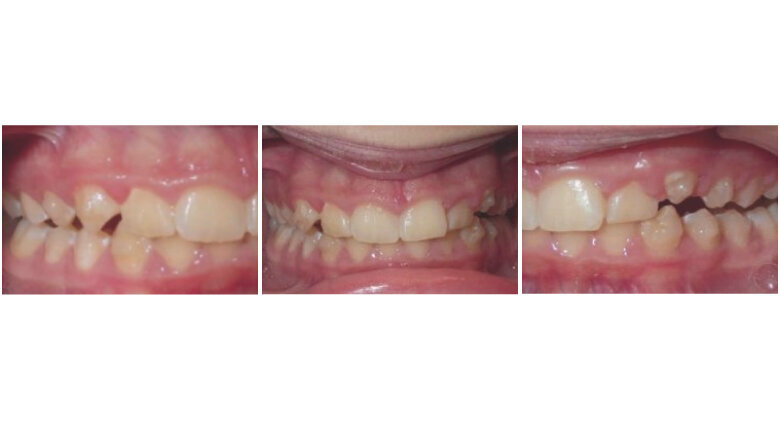

Initial Records

The patient is an 11 year 6 month old male with a chief concern of “overbite.” Diagnostic summary:

Class II, division 1 malocclusion (severe on the right, moderate on the left)

Deep overbite (moderate)

Moderate upper crowding

Mild lower crowding

The slightly retroclined upper incisors and flared lower incisors are consistent with dental compensations for a sagittal jaw discrepancy. The skeletal vertical dimension being within normal limits suggests that the deep bite is predominantly dental in nature.